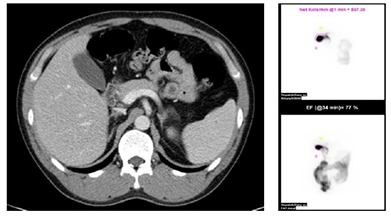

콜레스테롤 담석인지 여부를 확인하기 위해 복부 CT를 확인한다. 콜레스테롤 담석인 경우 CT에서 방사선 투과되어 음영이 관촬되지 않는다. 담낭의 정상 기능 확인을 위해 간담도 스캔을 시행한다. 간담도 스캔에서 담낭 기능이 정상이면 경구 담즙산 용해제를 복용한다. 담즙산 용해제 (UDCA)는 6개월~1년 이상 복용해야 하며, 담석의 완전 용해율은 40% 이하이다.